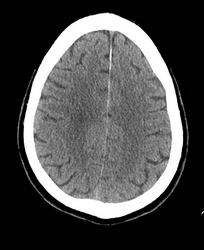

A 65-year-old woman with a past medical history of hypothyroidism and depression presented to an outside hospital with a profound right hemiparesis, right facial droop, aphasia, and right hemineglect. She was last seen well at 11 PM the previous evening and was therefore not considered eligible for IV tissue plasminogen activator (tPA). A representative image from her noncontrast head CT scan on admission is shown in Figure 1. She is now transferred to your Joint Commission–certified comprehensive stroke center for further care, arriving at 10 AM. What is the next appropriate intervention?

SELECT2 enrolled patients with a large infarct (Alberta stroke program early CT score [ASPECTS] of 3-5 or >50-mL volume) within 24 h of symptom onset, and RESCUE-Japan LIMIT enrolled patients with similar infarcts. The ASPECTS scale ranges from 0 to 10, with lower scores indicating larger volumes of ischemic tissue on initial noncontrast-enhanced CT scans. In both trials, the primary efficacy end point was the well-validated stroke outcome measure, the Rankin Scale, at 90 days, with minor differences in the method of analysis. In the RESCUE-Japan LIMIT trial, 31% vs 13% (intervention vs control) of patients achieved a favorable outcome (independent ambulation or better) on the Rankin Scale; in the SELECT2 trial, 38% vs 19% (intervention vs control) did. Although the SELECT2 trial closed on the basis of an unplanned interim analysis precipitated by publication of the results of the RESCUE-Japan LIMIT trial, the findings from both trials appear secure.